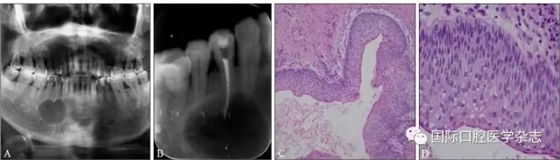

典型病例3 患者右下頜長包1月,臨床初診為44牙根尖周囊腫,治療期間反復(fù)換藥,伴右下頜脹痛,根管充填后轉(zhuǎn)診外科行根尖囊腫刮治A術(shù),術(shù)后病理示:右下頜骨KCOT伴感染(圖3)。

A:術(shù)前全景片,43—45根方透射影像,邊緣可見骨白線;B:術(shù)前充填根尖片;C、D:蘇木精-伊紅染色切片,示腫瘤襯里上皮表面為波浪狀的不全角化層,基底層細(xì)胞柵欄狀排列,細(xì)胞核遠(yuǎn)離基底膜,C圖 × 100,D圖 × 400。

圖 3 右下頜骨KCOT

Fig 3 KCOT in the rightmandible